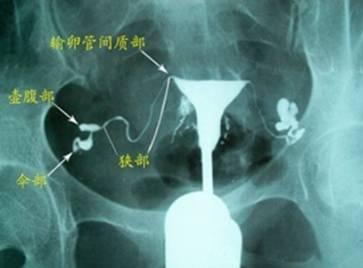

1、子宫输卵管造影(HSG)

HSG是首选的检查项目,通过向宫腔内注入造影剂,利用X线透视及摄片,根据造影剂在输卵管及盆腔内的显影情况,来了解输卵管是否通畅、阻塞部位及宫腔形态的一种检查方法。其操作简易、创伤小、价廉,在显示子宫腔及输卵管腔形态方面有着重要价值,且造影剂对输卵管粘膜的具有一定的冲刷作用,油性造影剂可以机械性扩张膜性粘连,含碘的造影剂还对慢性输卵管炎中的炎性吞噬细胞有一定的抑制作用。然而,HSG对输卵管病变的评估能力仍然存在一定的局限性。一方面,受检者需接受小剂量的X射线辐射,通过X片上所显示的宫腔及输卵管腔内的碘油弥散程度反映宫腔形态及管腔通畅性,具有一定的假阳性率;另一方面,输卵管外观及管周情况无从得知。

(图 正常HSG图)